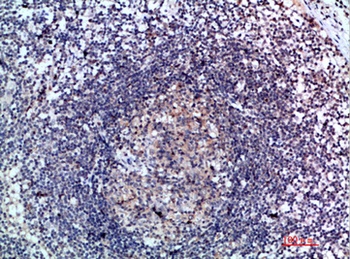

应用稀释比例:IHC-p 1:50-200, ELISA 1:10000-20000